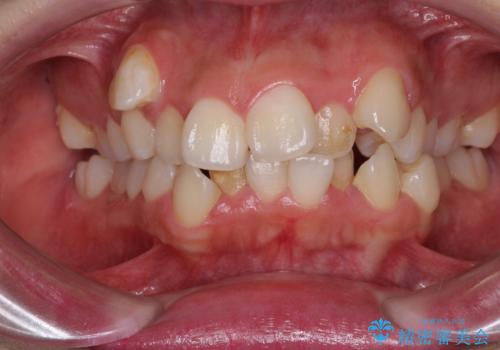

- 上下の前歯のデコボコと奥歯の反対咬合を気にして来院された患者様です。

インビザラインを用い、上下顎ともにIPR(歯と歯の間を削る)により叢生を改善することとしました。

奥歯の反対咬合は、骨格に由来するものであるため、改善できるところまで改善していくこととしました。

治療を長期化させたくないとのご要望があったので、左下の90度捻転した歯は、捻転した状態のゴールとしました。